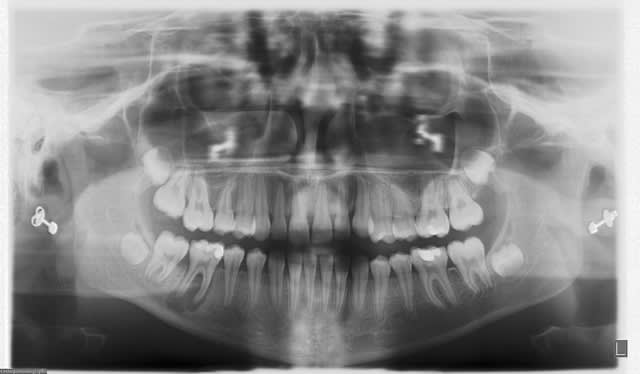

tu veux des images...en voilà 2...avant traitement et 6 mois plus tard...

C'est un beau début de cicatrisation.

Bel exemple du genre d'endo que je reprends au quotidien juste à coté de ta 7, lentulo fracturé et autres cochonneries.

et les instruments dans la 6, c'est toi? ;)

joli résultat quand même.